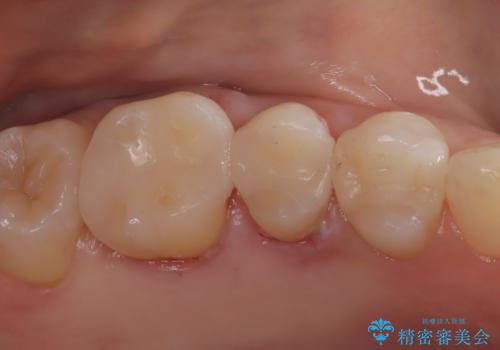

【セラミックインレー】メタルインレーの下が虫歯に

- 定期検診にて虫歯を認め、セラミックインレーにて治療を行いました。

メタルインレーの下には虫歯を認めることが多くありますが、今回のケースでも同じように虫歯を認めました。